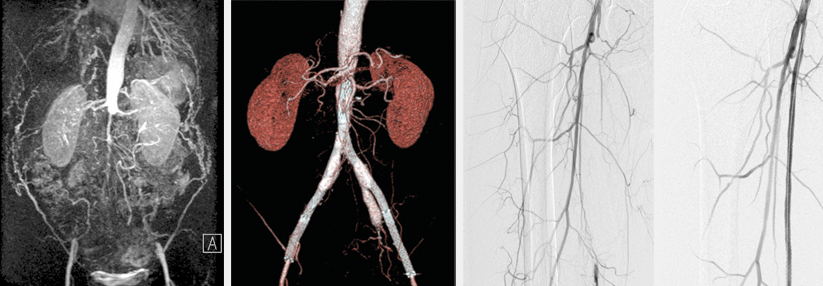

Die periphere arterielle Verschlusskrankheit (PAVK) ist Ausdruck einer generalisierten Atherosklerose. Patienten mit schweren Extremitätenmanifestationen oder weiteren internistischen Komorbiditäten erleiden überproportional häufig kardio- bzw. peripher-vaskuläre Komplikationen.

Dr. Eric Kaplovitch von der McMaster University in Hamilton und Kollegen werteten in einer Sekundäranalyse Daten der COMPASS-Studie aus. An der an 602 Zentren durchgeführten, internationalen randomisierten Doppelblindstudie nahmen insgesamt 27 395 Patienten mit einer Koronarerkrankung und/oder PAVK teil.